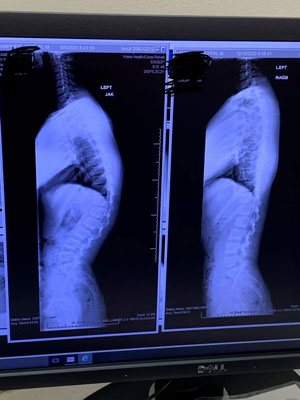

X-rays confirmed that Griffin had Scheuermann's kyphosis and mild scoliosis.

“A lot of people lump Scheuermann's kyphosis in with scoliosis but it’s different,” said Dr. Frino. “Scheuermann's kyphosis is a developmental deformity that occurs during adolescent growth. When vertebrae are wedged, it causes this condition. The vertebrae are normally rectangular-shaped and stacked on top of one another with cushioning in-between but if they wedge closer together in a triangular shape, it causes the spine to curve more than normal.”

Scheuermann's kyphosis presents as a more hunched appearance at the top of the spine and males are twice as likely to develop this type of kyphosis versus females.